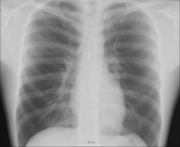

The history of anatomy has been characterized, over time, by a continually developing understanding of the functions of organs and structures in the body. Methods have also advanced dramatically, advancing from examination of animals through dissection of cadavers (dead human bodies) to technologically complex techniques developed in the 20th century.

Human anatomy, physiology and biochemistry are complementary basic medical sciences, which are generally taught to medical students in their first year at medical school. Human anatomy can be taught regionally or systemically; that is, respectively, studying anatomy by bodily regions such as the head and chest, or studying by specific systems, such as the nervous or respiratory systems. The major anatomy textbook, Gray's Anatomy, has recently been reorganized from a systems format to a regional format, in line with modern teaching methods. A thorough working knowledge of anatomy is required by all medical doctors, especially surgeons, and doctors working in some diagnostic specialities, such as histopathology and radiology.